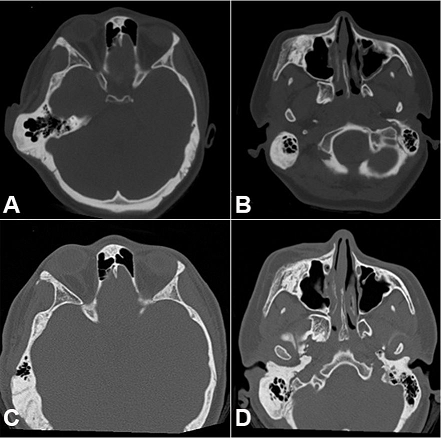

Neither patient exhibited trauma and/or associated infections, and both had normal laboratory test findings. The facial CT images of patient 1 showed an expansive lesion with the ground glass appearance that involved the skull base and the right maxillary, zygomatic, sphenoidal, temporal, frontal, and mandibular bones ( Figure 3).

In case of patient 2, because of the early development and slight facial deformity, a clinical follow-up protocol was selected. During the growth spurt between 12 and 13 years of age, she developed significant occlusal alterations, facial asymmetry, and difficulty in supporting her eyeglass stem because of sharp growth in the right mastoid apophysis. Laboratory test findings were within normal limits, and bone scintigraphy showed intense osteogenic activity on the right side of the skull. CT revealed volumetric osteofibrous thickening of the maxillary, mandibular, zygomatic, sphenoidal, temporal, mastoid, and parietal bones, with preservation of the internal acoustic meatus, optic canal, and stylomastoid foramen.